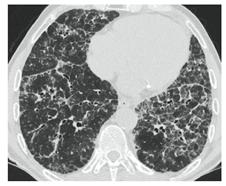

2. Наличие клинических проявлений, указанных в п. 1, в сочетании с характерными изменениями в легких по данным компьютерной томографии (КТ) (см. Приложение 1 настоящих рекомендаций) вне зависимости от результатов однократного лабораторного исследования на наличие РНК SARS-CoV-2 и эпидемиологического анамнеза.

- Изменения при КТ (рентгенографии), типичные для вирусного поражения (объем поражения минимальный или средний; КТ 1-2)

- Изменения в легких при КТ (рентгенографии), типичные для вирусного поражения (объем поражения значительный или субтотальный; КТ 3-4)

- Изменения в легких при КТ (рентгенографии), типичные для вирусного поражения критической степени (объем поражения значительный или субтотальный; КТ 4) или картина ОРДС.

КТ имеет высокую чувствительность в выявлении изменений в легких, характерных для COVID-19. Применение КТ целесообразно для первичной оценки состояния ОГК у пациентов с тяжелыми прогрессирующими формами заболевания, а также для дифференциальной диагностики выявленных изменений и оценки динамики процесса. КТ позволяет выявить характерные изменения в легких у пациентов с COVID-19 еще до появления положительных лабораторных тестов на инфекцию с помощью МАНК. В то же время, КТ выявляет изменения легких у значительного числа пациентов с бессимптомной и легкой формами заболевания, которым не требуется госпитализация. Результаты КТ в этих случаях не влияют на тактику лечения и прогноз заболевания при наличии лабораторного подтверждения COVID-19. Поэтому массовое применение КТ для скрининга асимптомных и легких форм болезни не рекомендуется.